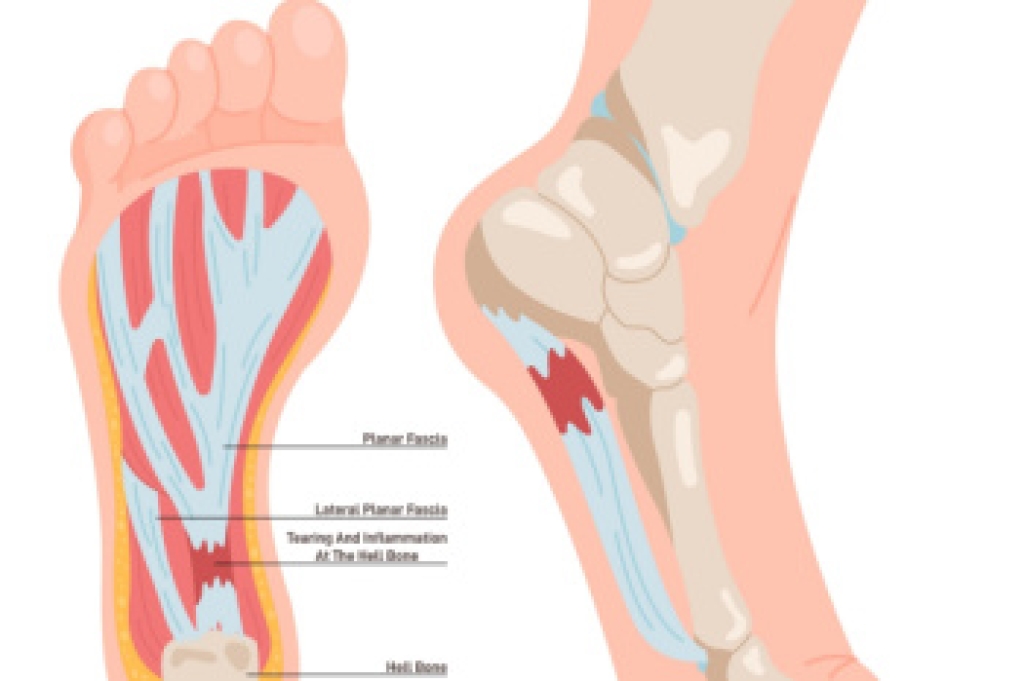

Chronic plantar fasciitis occurs when the thick band of tissue on the bottom of the foot, known as the plantar fascia, remains inflamed and painful over an extended period of time. An endoscopic plantar fasciotomy is a minimally invasive surgical procedure used to treat chronic plantar fasciitis that has not improved with conservative care. During the procedure, a small camera and specialized instruments are inserted through tiny incisions to release part of the fascia, reducing tension and inflammation. This method allows for less tissue disruption and faster healing. Recovery usually takes a few weeks, with gradual return to normal activities. If you have chronic plantar fasciitis, it is suggested that you consult a podiatrist who can explore effective relief options for ongoing heel pain.

Surgical techniques have also become increasingly sophisticated. Techniques like endoscopic surgery allow for smaller incisions and faster recovery times.